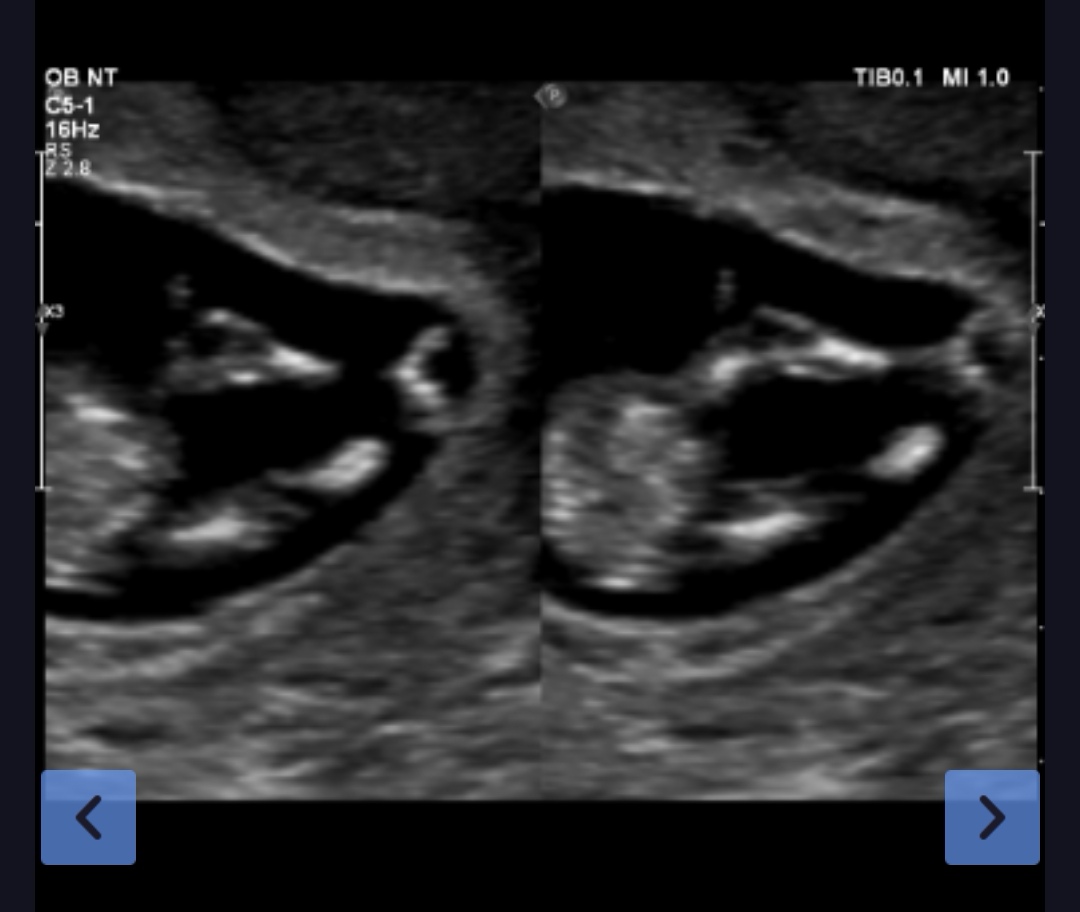

这照片能看出是男宝还是女宝吗

这照片能看出是男宝还是女宝吗?